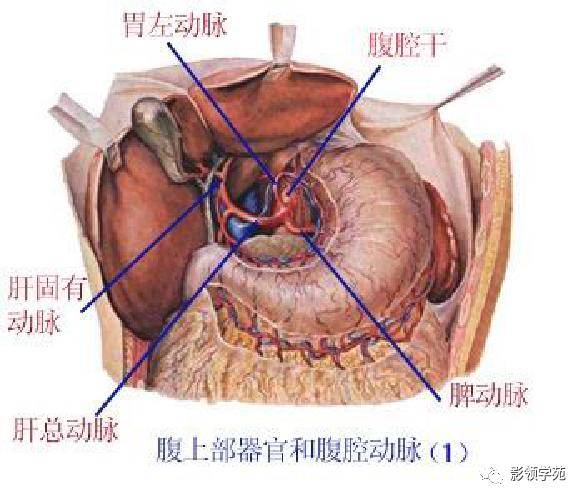

腹部动静脉

腹部动静脉